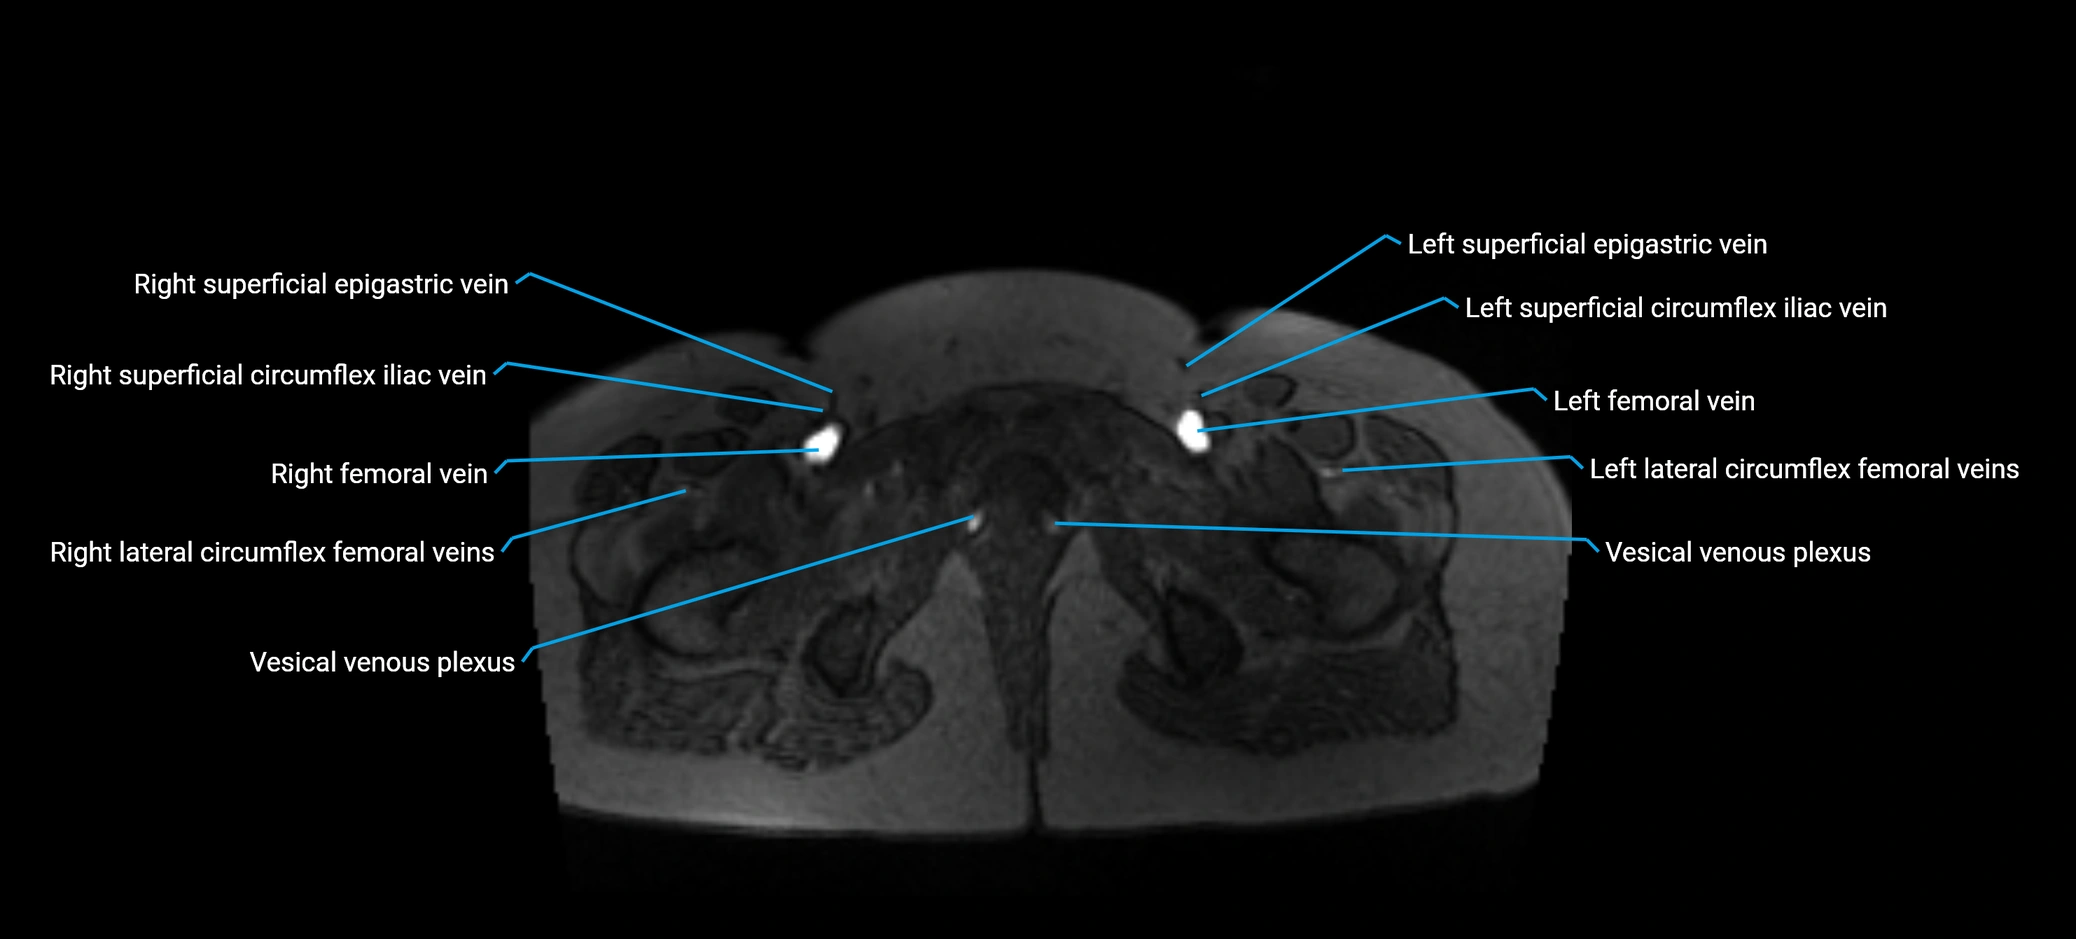

MRI image

image